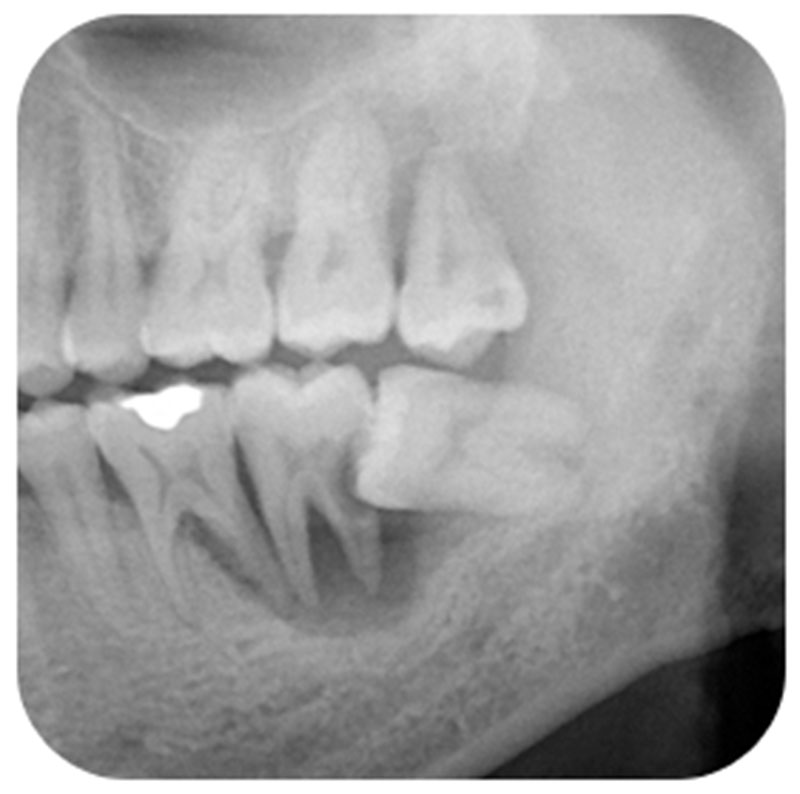

左下顎水平智齒造成前面的第二大臼齒牙根蛀牙和牙周病,前面的第二大臼齒牙根蛀牙往往沒辦法填補,嚴重的需要拔牙。

左下水平阻生智齒,造成鄰牙嚴重的牙周病和蛀牙,牙周病甚至進展到第一大臼齒,到這樣的程度,不但智齒 ,連第一大臼齒,第二大臼齒都沒辦法留,需要拔牙,實在得不償失。